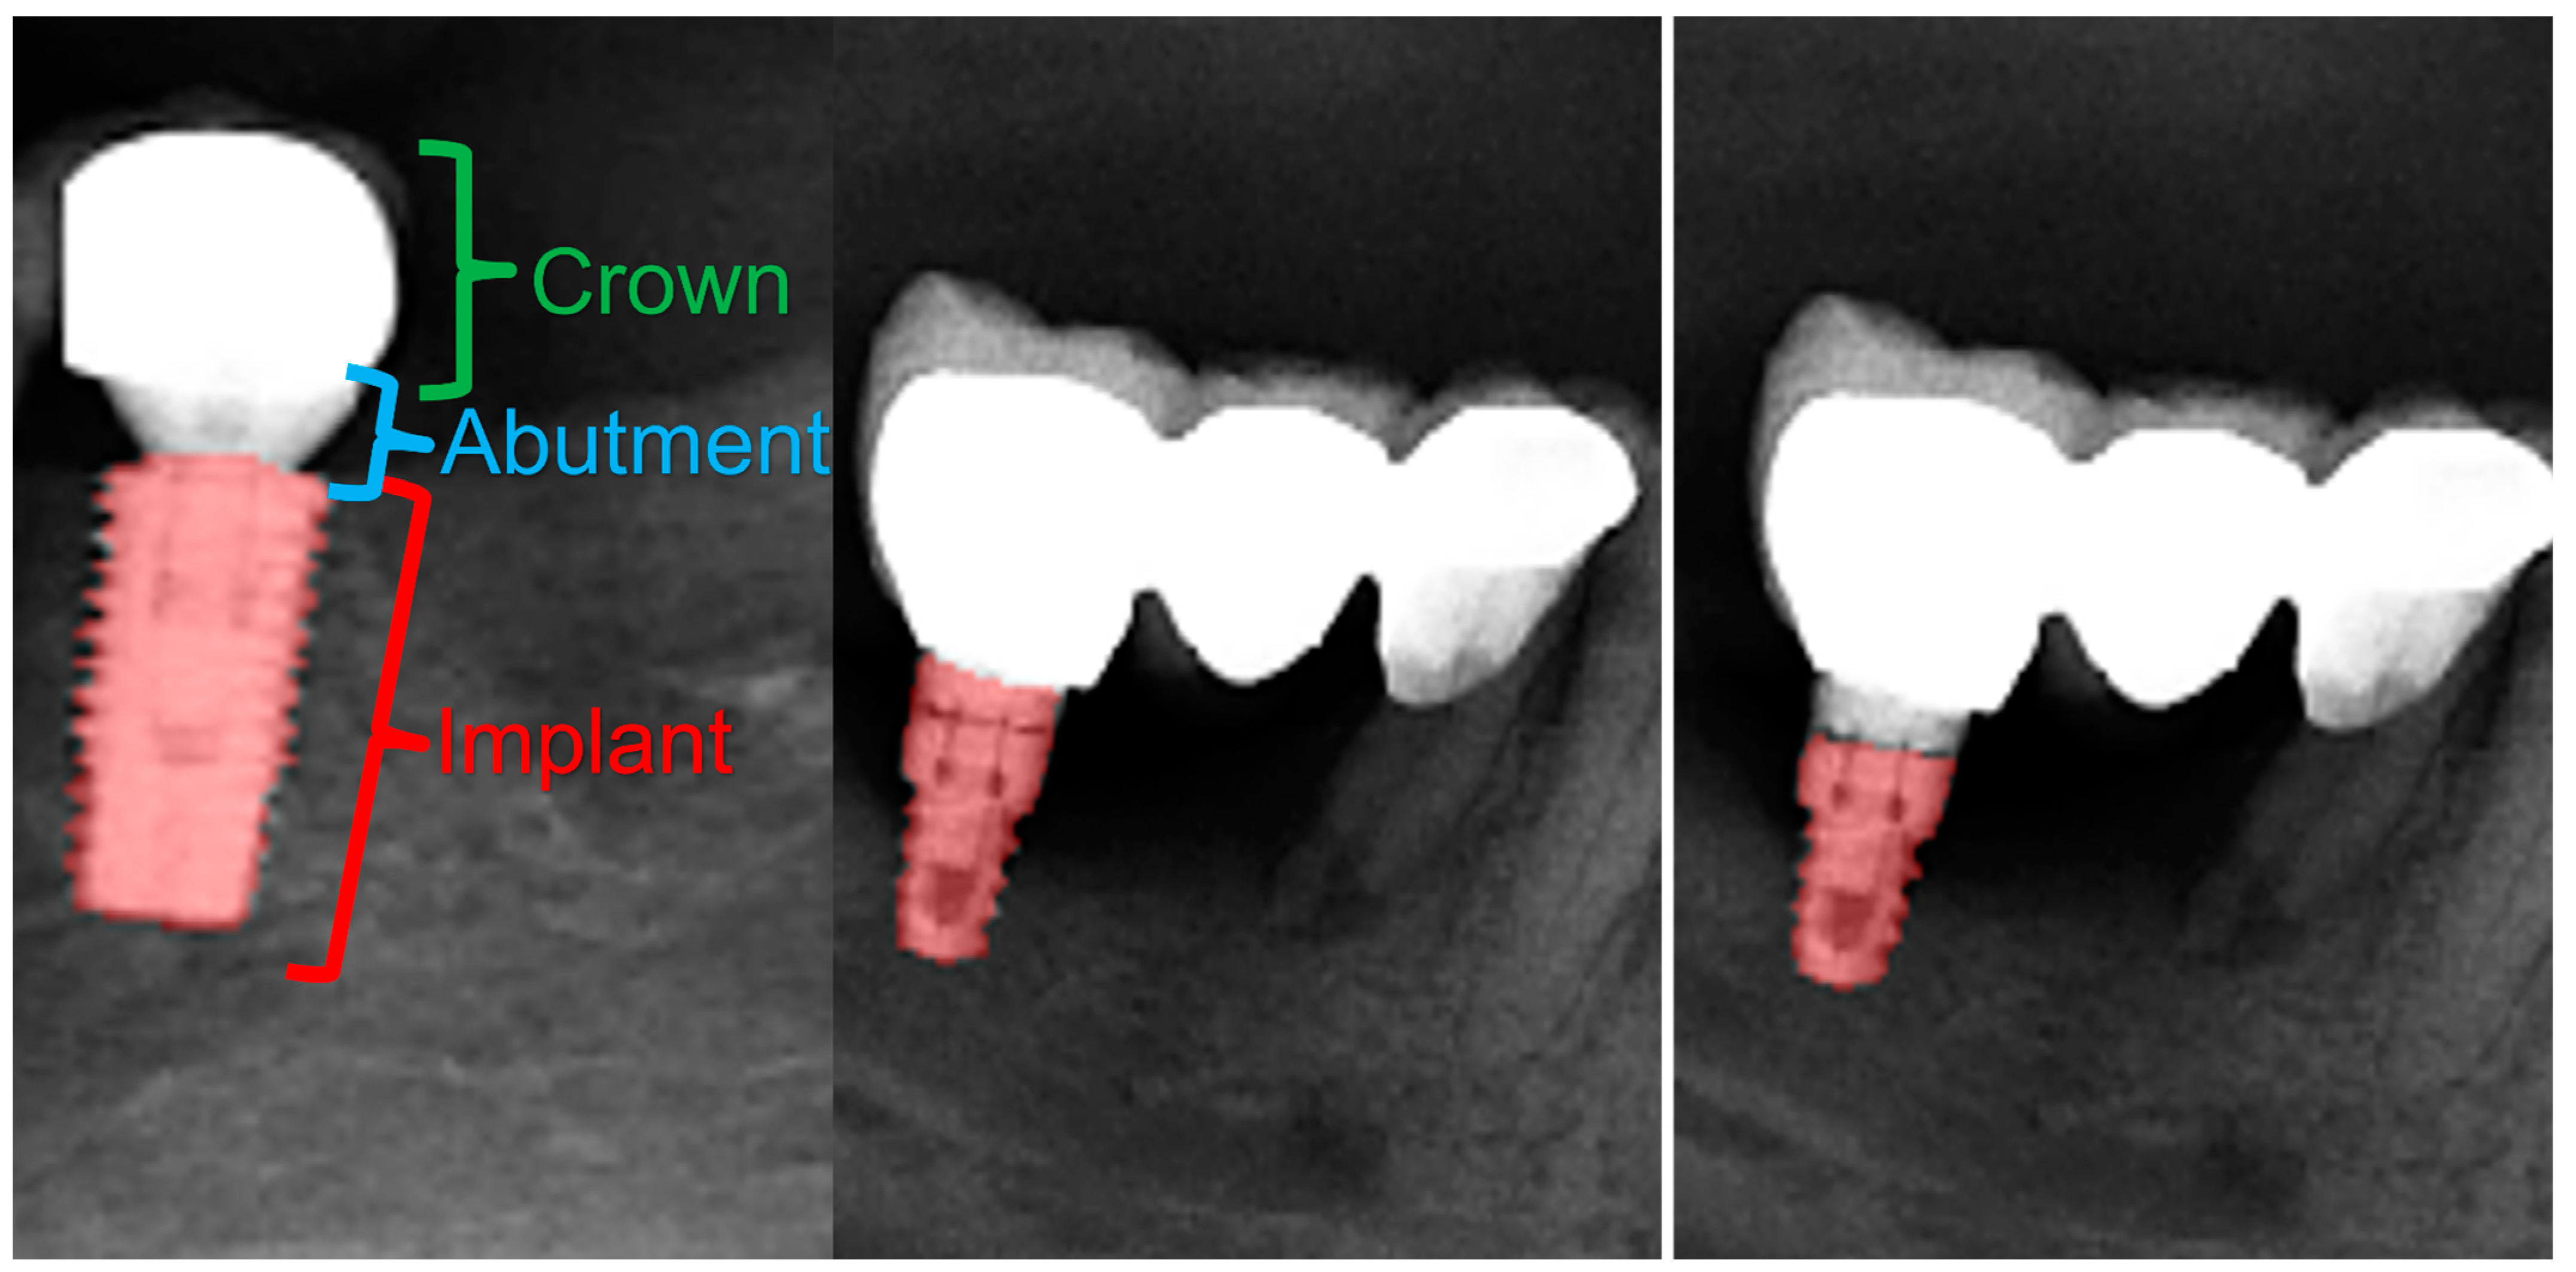

All of the objects mentioned above were segmented by determining their margins by creating points, and the model was trained separately for each of the structures with those segmentations (Figure 1).

Figure 1.

Manual segmentation process of the dental implants. Note the precision for the dental implant’s grove segmentation in order to achieve higher accuracy and DSC.